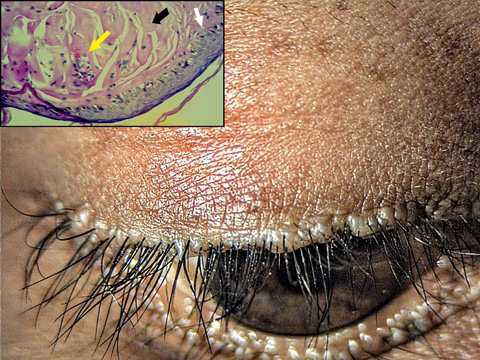

Moniliform blepharosis in lipoid proteinosis